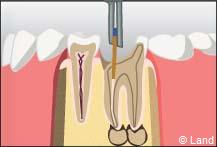

La pulpe est atteinte par la progression de la carie. Il y a donc un risque non négligeable de voir apparaître un foyer infectieux au bout de la racine.

1° Le chirurgien-dentiste va donc procéder à la dévitalisation* de la dent ; en clair il va extirper de la partie centrale de la dent avec les instruments adéquats, soit manuellement soit mécaniquement, la pulpe dentaire constituée de filets nerveux et de très fins vaisseaux sanguins. Cette étape permet d’enlever la totalité des tissus nécrosés ou infectés et de procéder à un nettoyage soigneux anti bactérien.